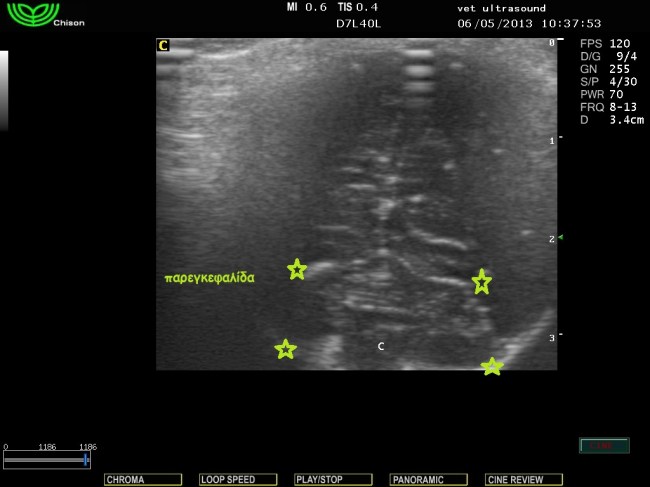

εγκάρσια τομή τελείως κάθετη στον επιμήκη άξονα του κρανίου.